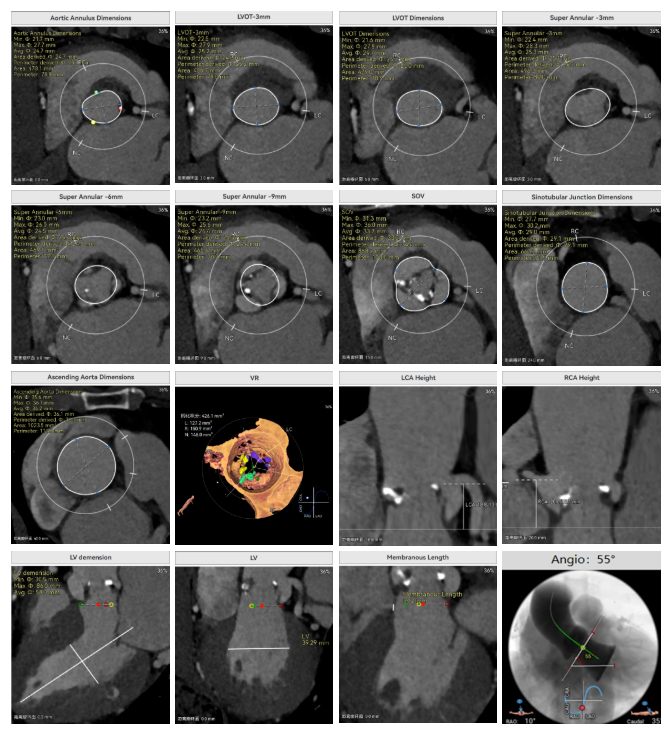

罗建方教授 广东省人民医院(点击查看专家详细简历) 设计本为临床需,耐久守护好芳华:任何医疗产品的设计初衷与最终归宿,都应落在 “临床获益” 这一核心上。尤其在 TAVR 领域,年轻患者预期寿命长,术后瓣膜的长期性能直接关乎其生活质量与生存预后。瓣膜耐久性问题,是落到临床实践中亟待突破的关键课题。传统瓣膜在长期使用中,可能因结构老化、功能退化等问题,难以满足年轻群体数十年的健康需求,二次手术风险也随之攀升。因此,产品设计必须直面这一临床痛点:通过材料革新增强抗钙化性能及生物相容性,以技术突破延长瓣膜有效使用寿命。此次临床应用的预装干瓣Prostyle A®是TAVR领域的革新理念,干瓣预期会为临床提供更耐久性的保障,实现了与临床需求的精准对接,为年轻群体的瓣膜治疗提供更坚实的保障。 李捷教授 广东省人民医院(点击查看专家详细简历) 干瓣技术求革新,性能兼顾护临床:干瓣的技术革新在创新的同时需要和临床实际需求深度耦合,兼顾TAVR术中的核心考量点。临床操作中,瓣膜能否顺利过弓,直接影响手术效率与安全性。Prostyle A®短瓣架设计及第二台阶的柔顺设计,术中操作丝滑;同时,瓣膜植入后的径向支撑力必须平衡得当,才能实现稳定锚定;释放后造影显示:瓣膜形态舒展,轻度瓣周漏,舒张压升高,冠脉开口未受影响;瓣周漏是影响术后效果的关键隐患,双层裙边设计通过多重密封机制降低反流风险,为患者长期获益筑牢防线。这些性能的协同优化,最终目的是让干瓣在临床中真正做到 “好用、耐用、安全用”,为患者预后提升提供坚实支撑。 患者病史 患者因 “活动后气促伴头晕 2 月” 入院。 现病史:2月前无诱因出现活动后气促,休息后缓解,伴头晕,夜间阵发性呼吸困难。超声检查发现:主动脉瓣重度狭窄并重度返流(跨瓣流速 4.3m/s,峰值压差 73mmHg);主动脉 + 冠状动脉 CTA 提示主动脉瓣显著钙化,升主动脉及分支粥样硬化,冠状动脉轻度狭窄(RCA 狭窄 30-40%)。 既往史:高血压病史 15 年,规律服药,血压控制稳定。 术前诊断:非风湿性主动脉瓣狭窄伴关闭不全(重度)、心功能 II 级(NYHA)、高血压病 2 级(高危)、冠状动脉粥样硬化。 术前CT 三叶瓣,瓣叶增厚中度钙化,右无交界钙化粘连,瓣环径25.1mm,LVOT 25.1mm,直筒型结构;窦部空间足够,升主未见增宽,瓣环水平夹角55°;冠脉开口位置佳,无冠脉风险;入路散在钙化、外周双侧入路无明显迂曲,双侧内径可、中分叉,左右侧均能够支持20F 大鞘通过。 造影角度及入路 手术策略 右侧股动脉为主入路,左侧为辅助入路;使用20球囊预扩,准备AV26瓣膜,冲洗口朝向3点钟方向送入输送系统性能,初始定位真实瓣环0位释放,最终锚定约瓣下3mm,工作位评估瓣膜稳定性与冠脉情况。 手术过程 根部造影 20mm 球囊预扩无明显腰征 术中使用26号瓣膜,瓣膜释放贴边迅速 80% 工作位观察瓣膜位置良好 释放后造影显示:瓣膜形态舒展,轻度瓣周漏,舒张压由术前30mmHg升为 60mmHg,冠脉开口未受影响。 术后超声:跨瓣流速降至1.6m/s,平均压差降至5 mmHg,心功能显著改善。 Prostyle A®预装干瓣——助力临床最优化解决方案: 1. 抗钙化与耐久性:Micro-EX™专利技术提升瓣膜抗钙化能力,适配患者瓣叶中度钙化的解剖特点,为长期疗效提供保障。 2. 柔顺过弓与精准定位:短瓣架设计 + 远端超滑涂层,确保患者输送系统过弓顺畅;瓣架流入端微直筒设计,让定位贴边更迅速,减少了手术时间; 3. 80% 可回收设计:便于术中调整观察,减少起搏时间,从而减少并发症。 4. 简化手术流程:预装设计缩短操作时间,20F 大鞘兼容外周入路,降低血管损伤风险。 · END ·